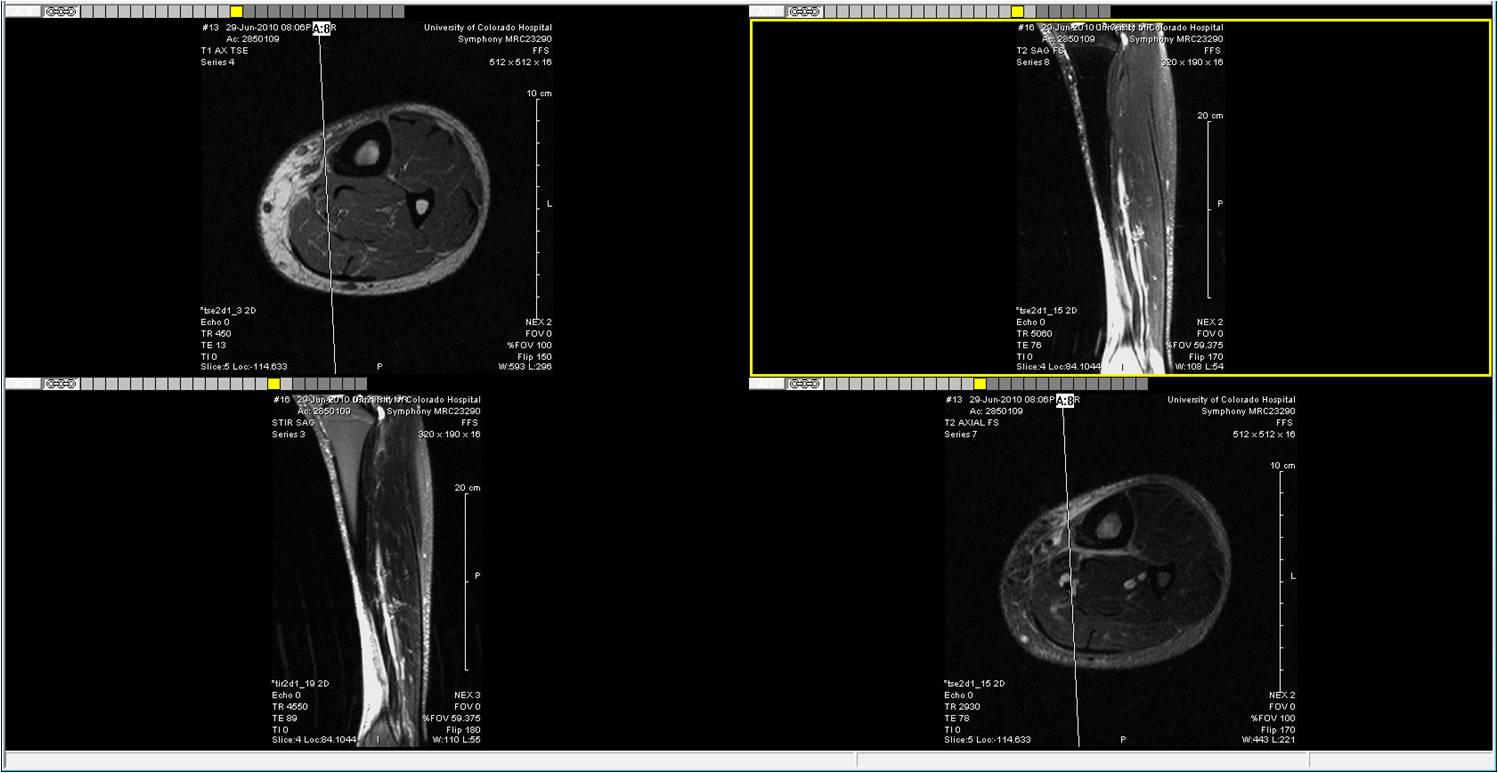

This aging crap sucks. After a really good training period leading up to the Estes Park 1/2 marathon, my left tibia/ankle/foot blew out. I held out hope that I could still run the 1/2, but the weekend of the event, my ankle was still swollen. After the hike, I had to ice the ankle and take 12 Motrin per day to reduce the swelling and pain.

So, it was off to the field of magnets for an image.

I'm not a medical doctor, but it looks like something isn't "right" around the tibia. Hopefully, my sports medicine doc will tell me I'm injured and how to fix it on Thursday. I told him during my initial visit that he has to keep me together through next year so that I can run a marathon at 50.

The radiologist and my sports medicine doctor finally reviewed the MRI. The tibia is fractured, which explains why my leg hurts and swells every day. No running for at least 3 months (yuk!). No bike, no elliptical, and no stairs for at least 6 weeks. No swimming for 3 weeks. Nothing. Crutches and a boot to move around for 6 weeks until we can see if the bone is healing. If not, I will need a pin inserted to help the healing.